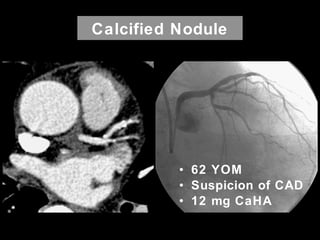

Calcified Nodule

• 62 YOM

• Suspicion of CAD

• 12 mg CaHA